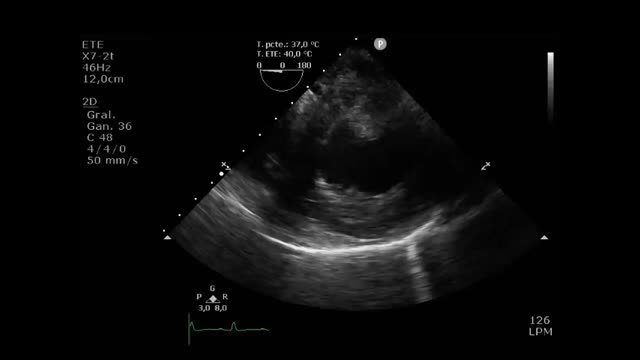

El postoperado de cirugía cardiaca (PC) presenta ciertas dificultades técnicas relacionadas con la limitación para la movilización del paciente: presencia de apósitos, drenajes, imposibilidad de utilizar la vía subxifoidea, dolor posquirúrgico, intubación, soporte ventilatorio, etc. (fig. 1). Son limitaciones técnicas que dificultan la adquisición de imágenes, que, junto con la presencia frecuente de coágulos loculados o de derrame pericárdico-pleural, podrían dificultar la interpretación del estudio ecográfico, precisando, en ocasiones, la combinación de otras técnicas para una adecuada evaluación.

Proyecciones más útilesEstudio cardiológicoEstá condicionado en ocasiones por las dificultades técnicas, y por ello no debe descartarse el ETE cuando el riesgo de un retraso en el diagnostico implica un empeoramiento del pronóstico. El examen debe abordar el mayor número de ventanas posibles y utilizar transductores con menor frecuencia para conseguir mayor penetración, en especial en pacientes obesos. Y si la situación clínica lo permite, inclinar ligeramente el paciente hacia la izquierda.

La ventana paraesternal y la ventana apical 4 cámaras y 2 cámaras nos dan un examen completo del ventrículo izquierdo (VI), así como los ejes transversales de la válvula aórtica y mitral, que permiten determinar insuficiencia residual o fugas paravalvulares al poderse alinear de manera correcta. El acceso subxifoideo permite una visión global de las cavidades derechas, del tamaño del ventrículo derecho (VD), de la función tricuspídea y del tamaño de la vena cava inferior; sin embargo, está muy condicionado por la salida de los drenajes mediastínicos y esternales.